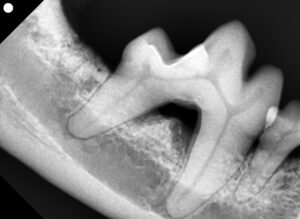

今回のワンちゃんは、小型犬で、左下顎の第三切歯と犬歯の間に歯肉の赤み、歯石沈着、歯の動揺が見られました。

歯科用レントゲンにて骨吸収が認められ、中等度の歯周病と診断。

幸いにも歯は保存可能と判断し、以下のような歯周外科を実施しました。